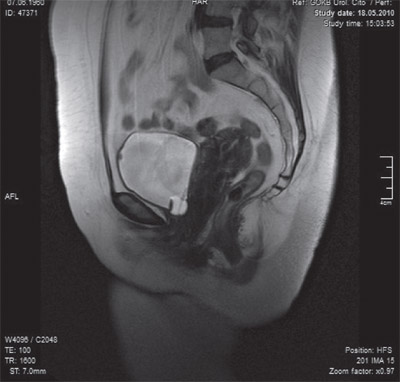

Степень опущения мочевого пузыря, уретры, влагалища и матки определя ли по смещению их относительно линии, соединяющей нижний край лонного сочленения и копчик (лонно-копчиковая линия, рис. 1 и 2).

Результаты и обсуждение. МРТ и МСКТ, полученные у больных со СНМ в сагиттальной плоскости в спокойном состоянии и на высоте пробы Вальсальвы, позволили оценить и документировать степень опущения пузырно-уретрального сегмента в см относительно лонно-копчиковой линии (рис. 1, 2 и 3).

Во всех случаях СНМ на томограммах неизменно определялось смещение уретро-пузырного сегмента вниз и кзади, кроме того, при СНМ на М-Р томограммах, выполненных на высоте пробы Вальсальвы, отмечалось истончение тканевых поддерживающих уретру структур.

Рис. 1 МРТ таза (срез в сагиттальной плоскости). Т-2 взвешенное изображение. В спокойном состоянии шейка мочевого пузыря находится на уровне лоннокопчиковой линии